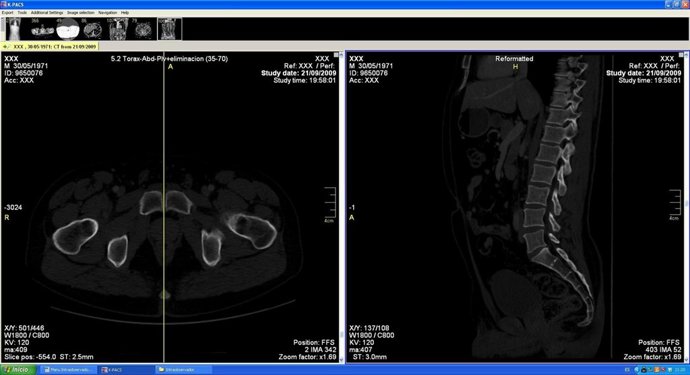

Ejemplo de selección del corte de estudio.

En estos estudios se identificaron los cortes sagitales de la superficie articular sinfisaria y del cuerpo del pubis, de manera que de cada estudio se obtuvieron un total de cuatro cortes: dos de cada superficie articular sinfisaria derecha e izquierda y otros dos de cada cuerpo del pubis.